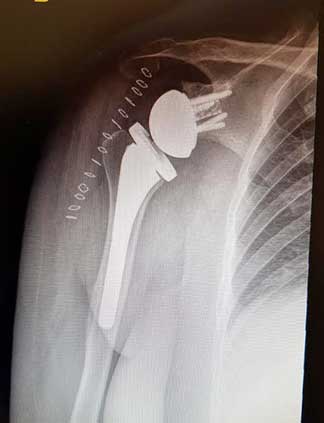

Radiografía postquirúrgica de prótesis reversa de hombro derecho.